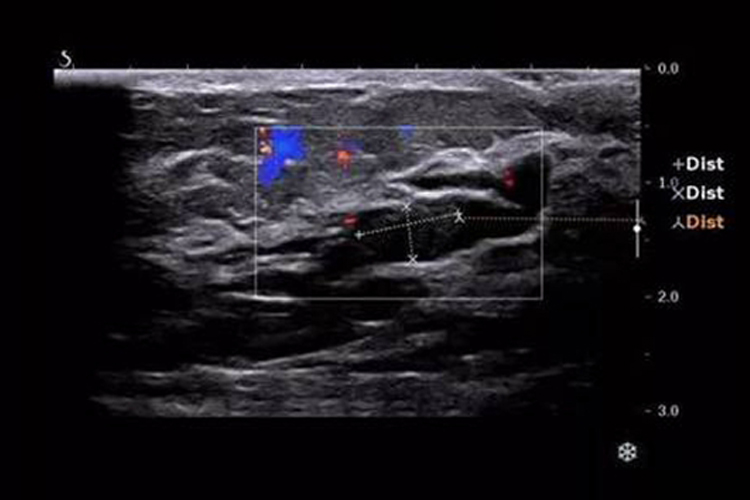

乳腺导管内乳头状瘤可通过超声检查辅助诊断,单发者表现为乳晕后区导管扩张,其近端可见实性低回声肿块,或表现为条索状、絮状弱回声充满管腔。另还可表现为囊实性肿块,临床可扪及肿块,但患者常无乳头溢液的临床表现。当病灶为多发者,可表现为双侧乳腺内多条树枝状分布的扩张导管,部分导管内可见单个或多个乳头状突起。